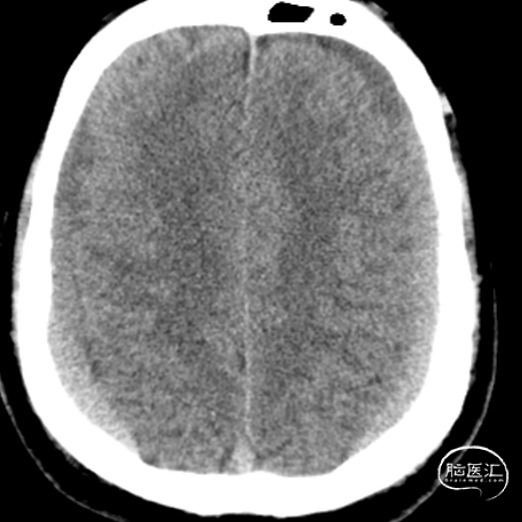

患者因“自发性双侧亚急性硬膜下血肿”收入功能神经外科,我科经过仔细全面检查,考虑诊断为“自发性低颅压头痛”并经MRI全脊柱水成像确定原因为寰枢椎之间有一处硬膜窦道,遂采用了精准微创的方法行C臂定位下硬脑膜漏口硬膜外血贴治疗术。术前患者一直卧床半月,术后第二天患者既症状明显改善下床活动,后患者治愈出院,未遗留神经并发症。2周后经MRI复查漏口已消失。本案例详细资料于2018.3.25日发表于《神外资讯》的 颅脑创伤-神经重症病例周刊(第59期)。

患者,女,36岁,因“头痛6天”入院于2002.5.19,入院后考虑“自发性低颅压头痛”,腰穿测压25mmH2O。行全脊髓MRI水成像未见异常,遂行全脊髓MRI造影术提示:颈1.2间左右两处瘘口分别位于颈1椎板上下缘。行DSA下精准靶向硬膜外血贴治疗后,患者第二天症状明显改善,第三天即痊愈出院。嘱患者两周后复查,因患者恢复满意,2周后患者不愿再做复查。